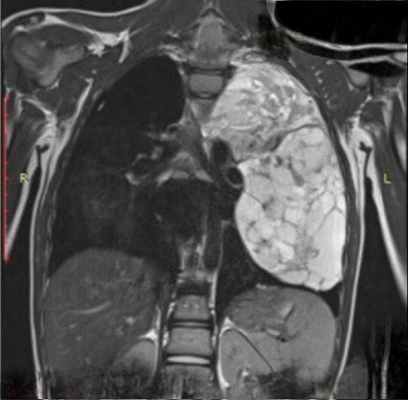

Обязательный перечень рентгенологических исследований включает рентгенографию грудной клетки, рентгенографию пищевода с контрастированием, компьютерную томографию. В большинстве случаев проведенное обследование позволяет установить локализацию рака средостения и распространенность процесса, заинтересованность органов грудной полости (легких, диафрагмы, аорты, грудной стенки). Уточнить состояние мягких тканей в зоне новообразования, выявить метастазы опухоли в лимфоузлы и легкие помогает МРТ.

Для того, чтобы поставить диагноз, пациента направляют на рентгенографию грудной клетки, пищевода с контрастированием и компьютерную томографию. Обследование позволяет установить точную локацию рака средостения, обширность процесса, поражение других органов грудной полости — легких, диафрагмы, аорты, грудной стенки. Узнать состояние мягких тканей в зоне новообразования, а также выявить метастазы опухоли в лимфоузлы и легкие дает возможность МРТ.